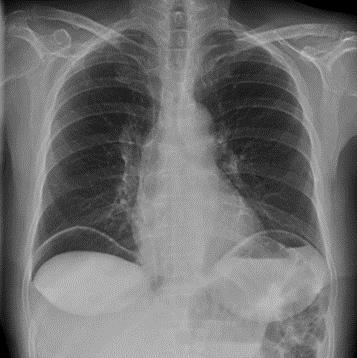

FAST: Estudio de ultrasonido que explora la zona perihepática, pericárdica, periesplénica, peripélvica en busca de la presión de líquido libre en cavidad abdominal (ENARM 2013).

LPD (Lavado peritoneal diagnóstico): estudio más específico pero invasivo (ENARM 2015, ENARM 2018). Es positivo si: 10 ml de aspirado sanguíneo inicial > 100.000 eritrocitos o > 500 leucocitos por mm3

Si el examen FAST no está disponible, se debe llevar a un paciente hemodinámicamente inestable al quirófano de inmediato.